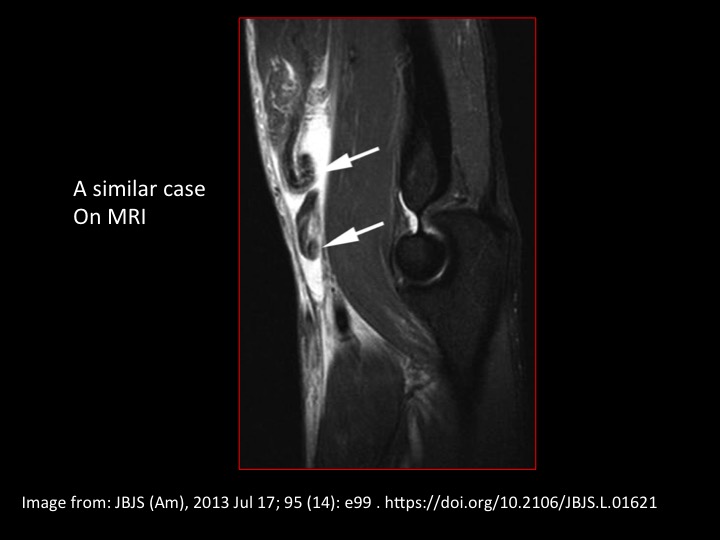

As is standard practice in the States, our US techs scan the patients and then review images with us. All too often (maybe because we are too busy, or maybe because were not entirely comfortable with MSK US) many of us are quick to accept what the technologists show us and base our reports on what is conveyed by their image labels and their scan notes. My (most excellent) technologist was amazed by this case, where she demonstrated a complete tear at the biceps myotendinous junction, And then a separate complete tear through the distal tendon. That made no sense. I needed to prove it and document the tear site. Slide 3 is the extended FOV showing the complete distal avulsion of the tendon off the radial tuberosity, retracted to the upper arm. The redundancy of the markedly retracted tendon created the confusing image (similar injury on MRI slide 4). Since the diagnosis was obvious to the referrer, our only job was to identify the site of the tear and the length of the defect. If we couldt get that right, wed have been utterly useless.